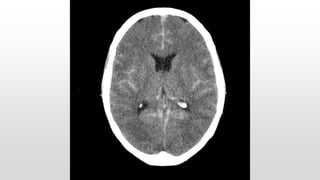

This document discusses various cases of collapse and syncope. It defines collapse as transient loss of consciousness with loss of postural tone and full recovery. Syncope is defined as loss of postural tone with or without loss of consciousness and full recovery. It then discusses the multiple potential causes of collapse and syncope including toxicological, cardiac conduction abnormalities, structural cardiac issues, autonomic dysfunction and more. It then goes through 9 case examples, discussing important questions to ask, potential tests and interventions for each case.